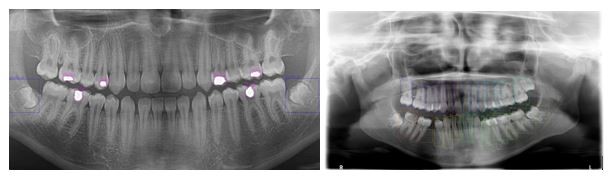

The issues described Section 1 are open problems, which were challenging to overcome. Studies have attempted to pinpoint tooth location and enumeration on panoramic X-ray images. However, identifying multiple concurrent treatments remains an unsolved task. Each treatment and enumeration in the maxillae and the mandible were manually annotated by labeling the bounding box in the LabelImg program (13). The locations of diagnosis and numbering were marked by drawing a bounding box, and all teeth were labeled in our study (Fig. 1). The 5,126 radiographs in the dataset contained 56,520 tooth treatments and 95,066 tooth numbers, which were used as the ground truth data for training and testing. The test data comprised 10% of the panoramic radiographs.

Figure 1. Detections from treatment (Blue labels Impacted Tooth and Purple labels Filling) and enumeration data set.

This study aimed to identify tooth numbering and dental treatments in X-ray images, such as implants, infections, caries, fillings, root canal treatments, extracted teeth, impacted teeth, bridges, and crowns (Fig. 2 and 3).

Figure 2. 2D images for tooth treatment.